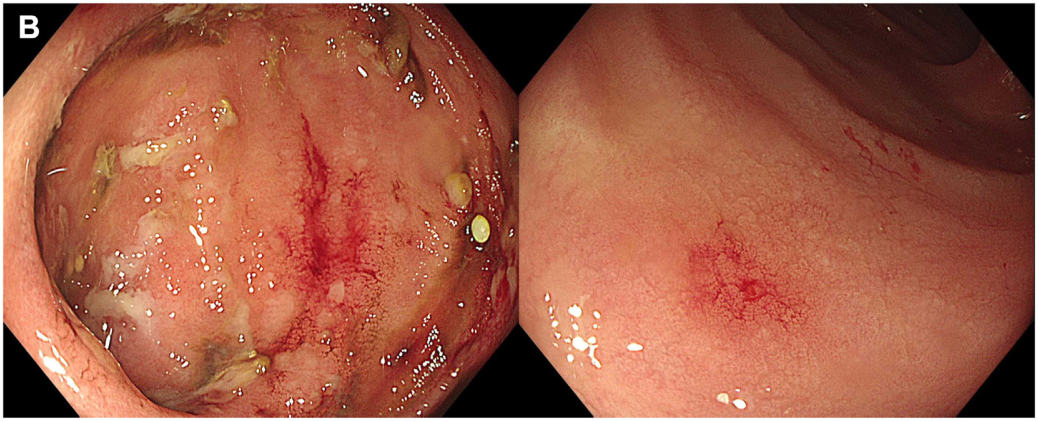

造血干细胞移植术后腹痛+黏液血便:这个极易误诊的肠道“隐形杀手”,千万别忽视!

病史摘要:患者为 36 岁男性,主诉持续性腹痛 5 个月,伴黏液血便 1 个月,后进展为不完全性肠梗阻。3 年前确诊急性 B 淋巴细胞白血病,并行异基因造血干细胞移植,移植后发生累及口腔及皮肤的急性移植物抗宿主病,使用环孢素、芦可替尼治疗至腹痛发作。 诊疗过程:实验室检查示 D - 二聚体及超敏 C 反应蛋白升高,其余正常。结肠镜见乙状结肠及直肠黏膜充血等改变,CT